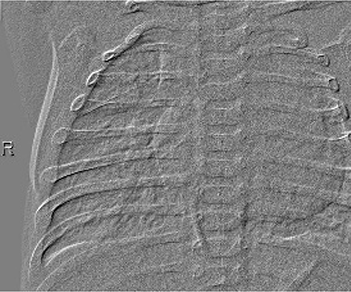

Table 6 Fused image output.

From: Multimodal medical image fusion combining saliency perception and generative adversarial network